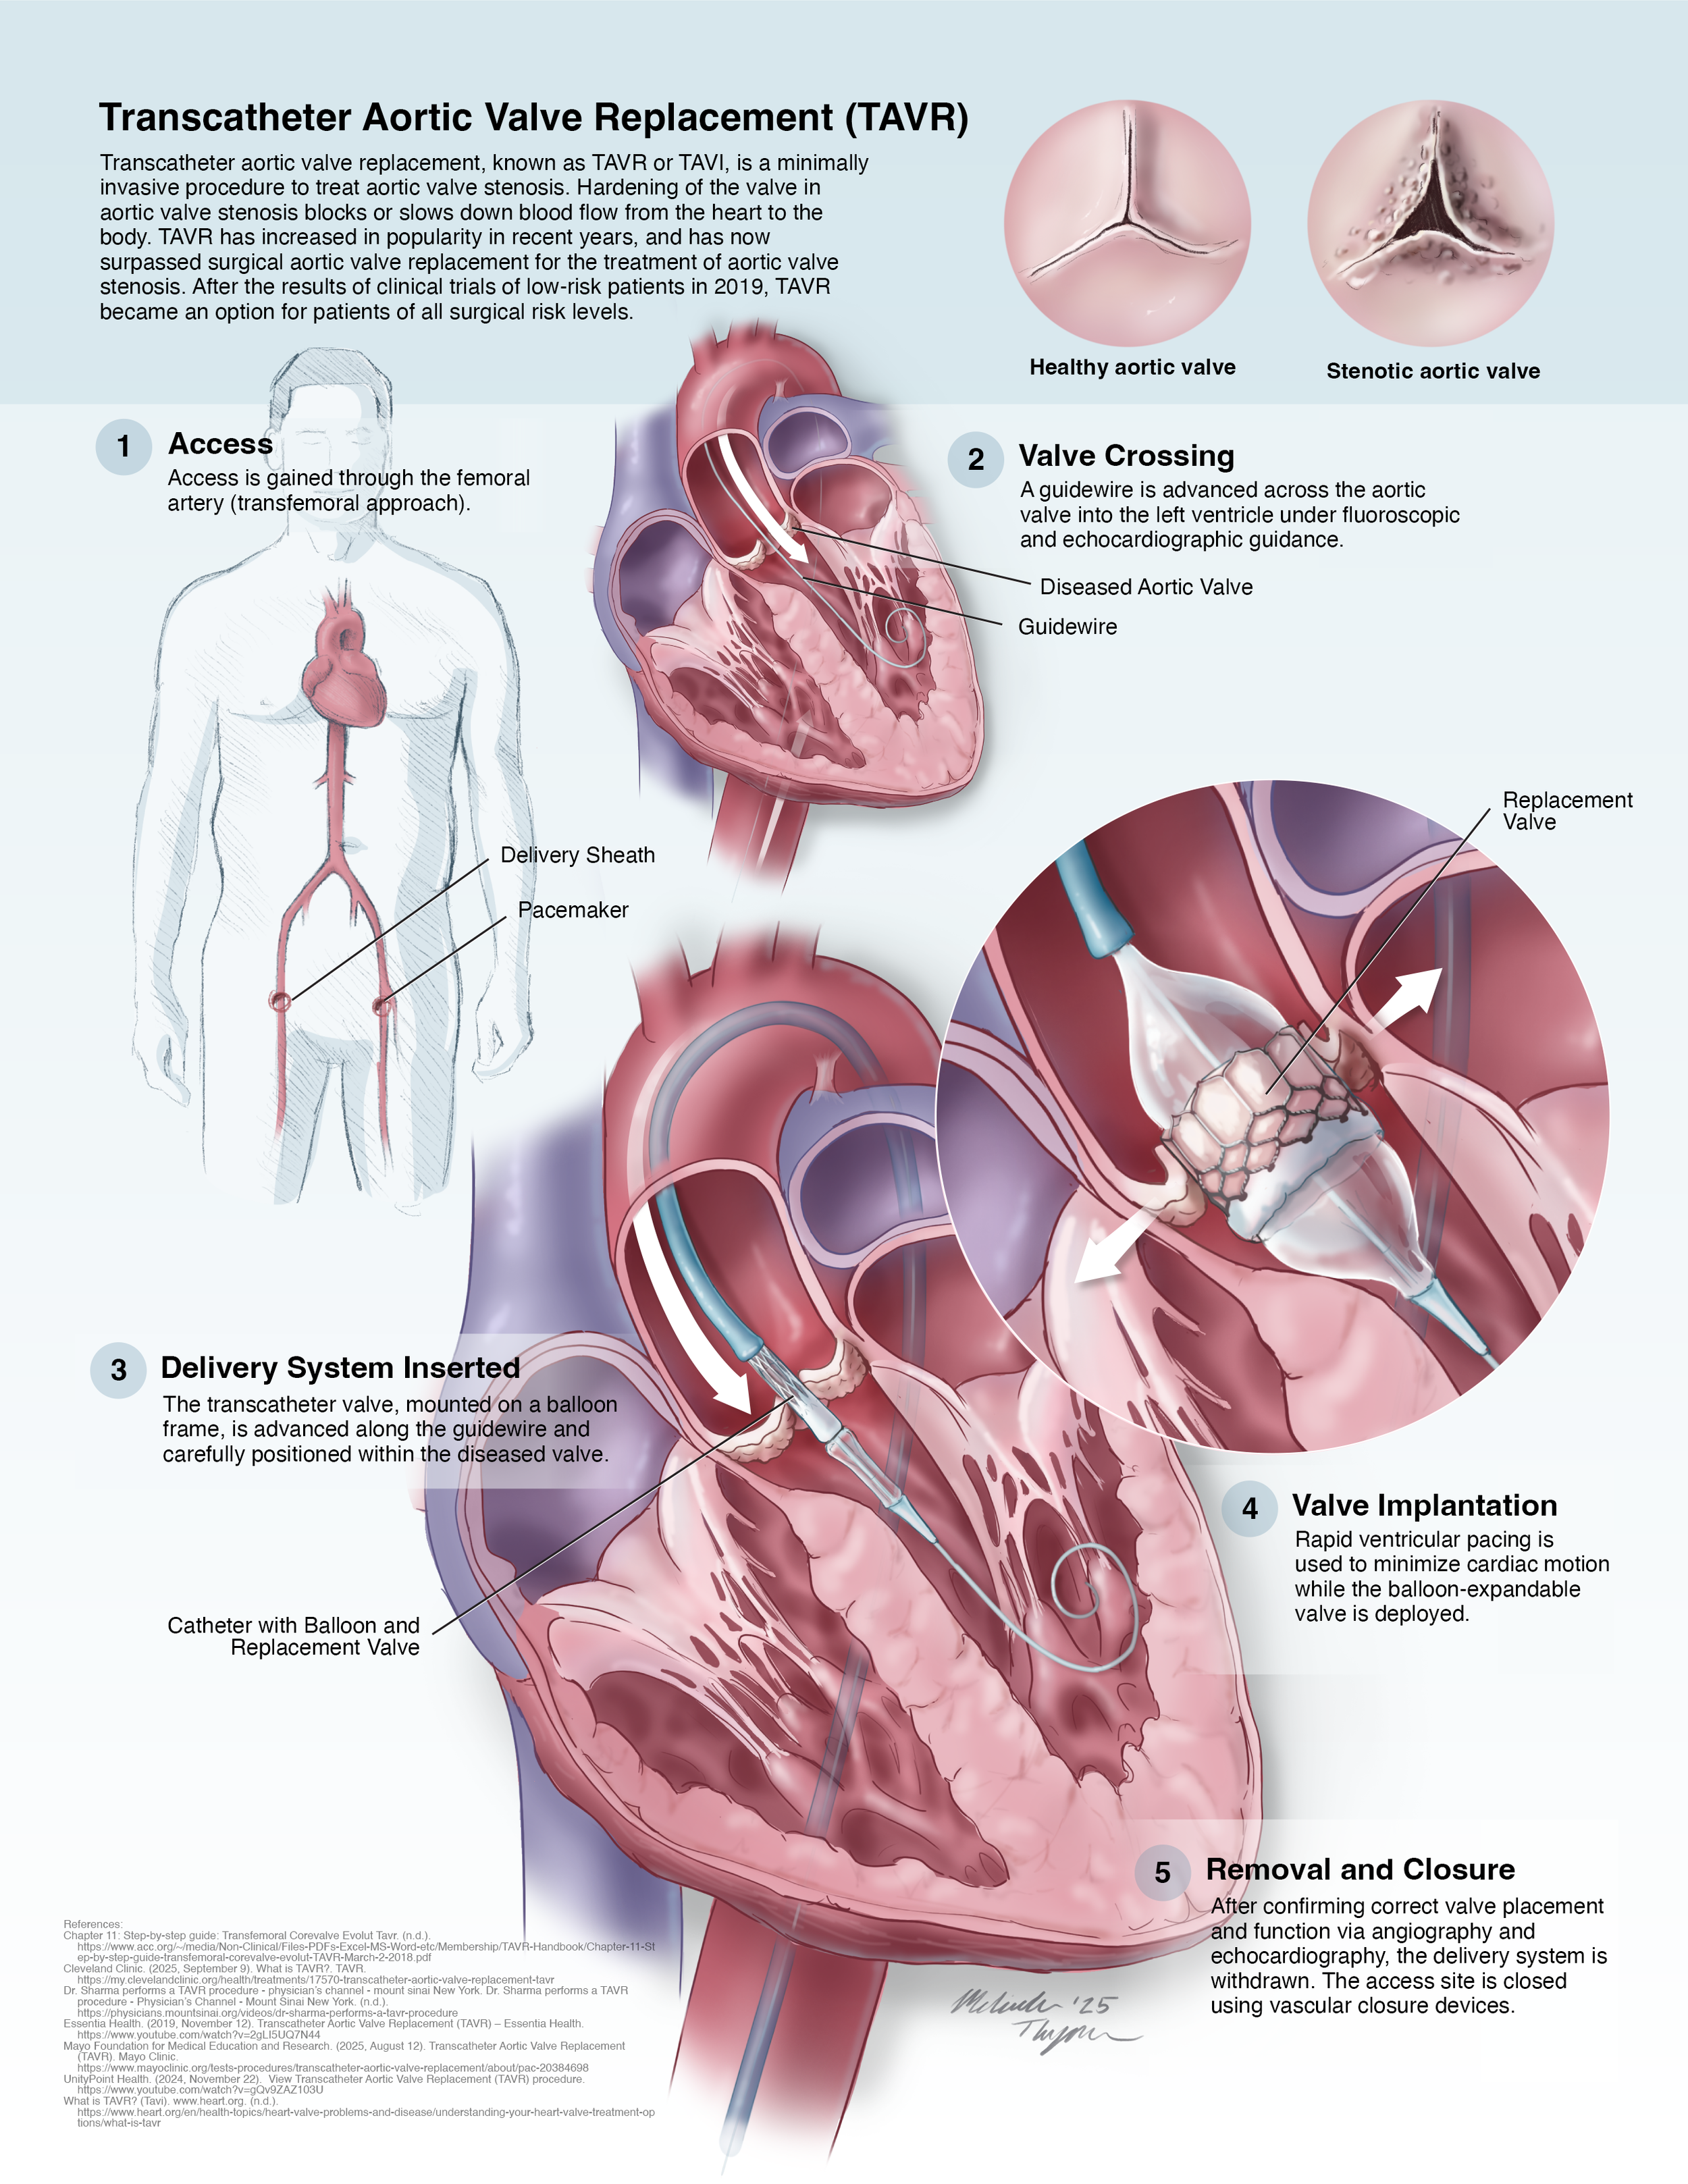

Academic Surgical Illustration: Transcatheter Aortic Valve Replacement - Illustrated Procedure